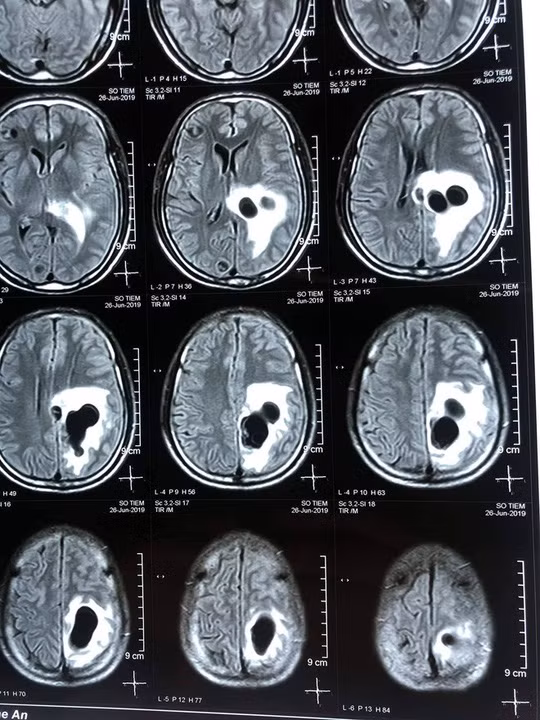

| Não nạn nhân có nhiều sán làm tổ do ăn tiết canh. |

Qua thăm khám và chụp CT não, các bác sĩ phát hiện có 5 ổ sán nằm rải rác trong não ông S., trong đó có một ổ sán lớn trên đỉnh não của bệnh nhân gây phù não.